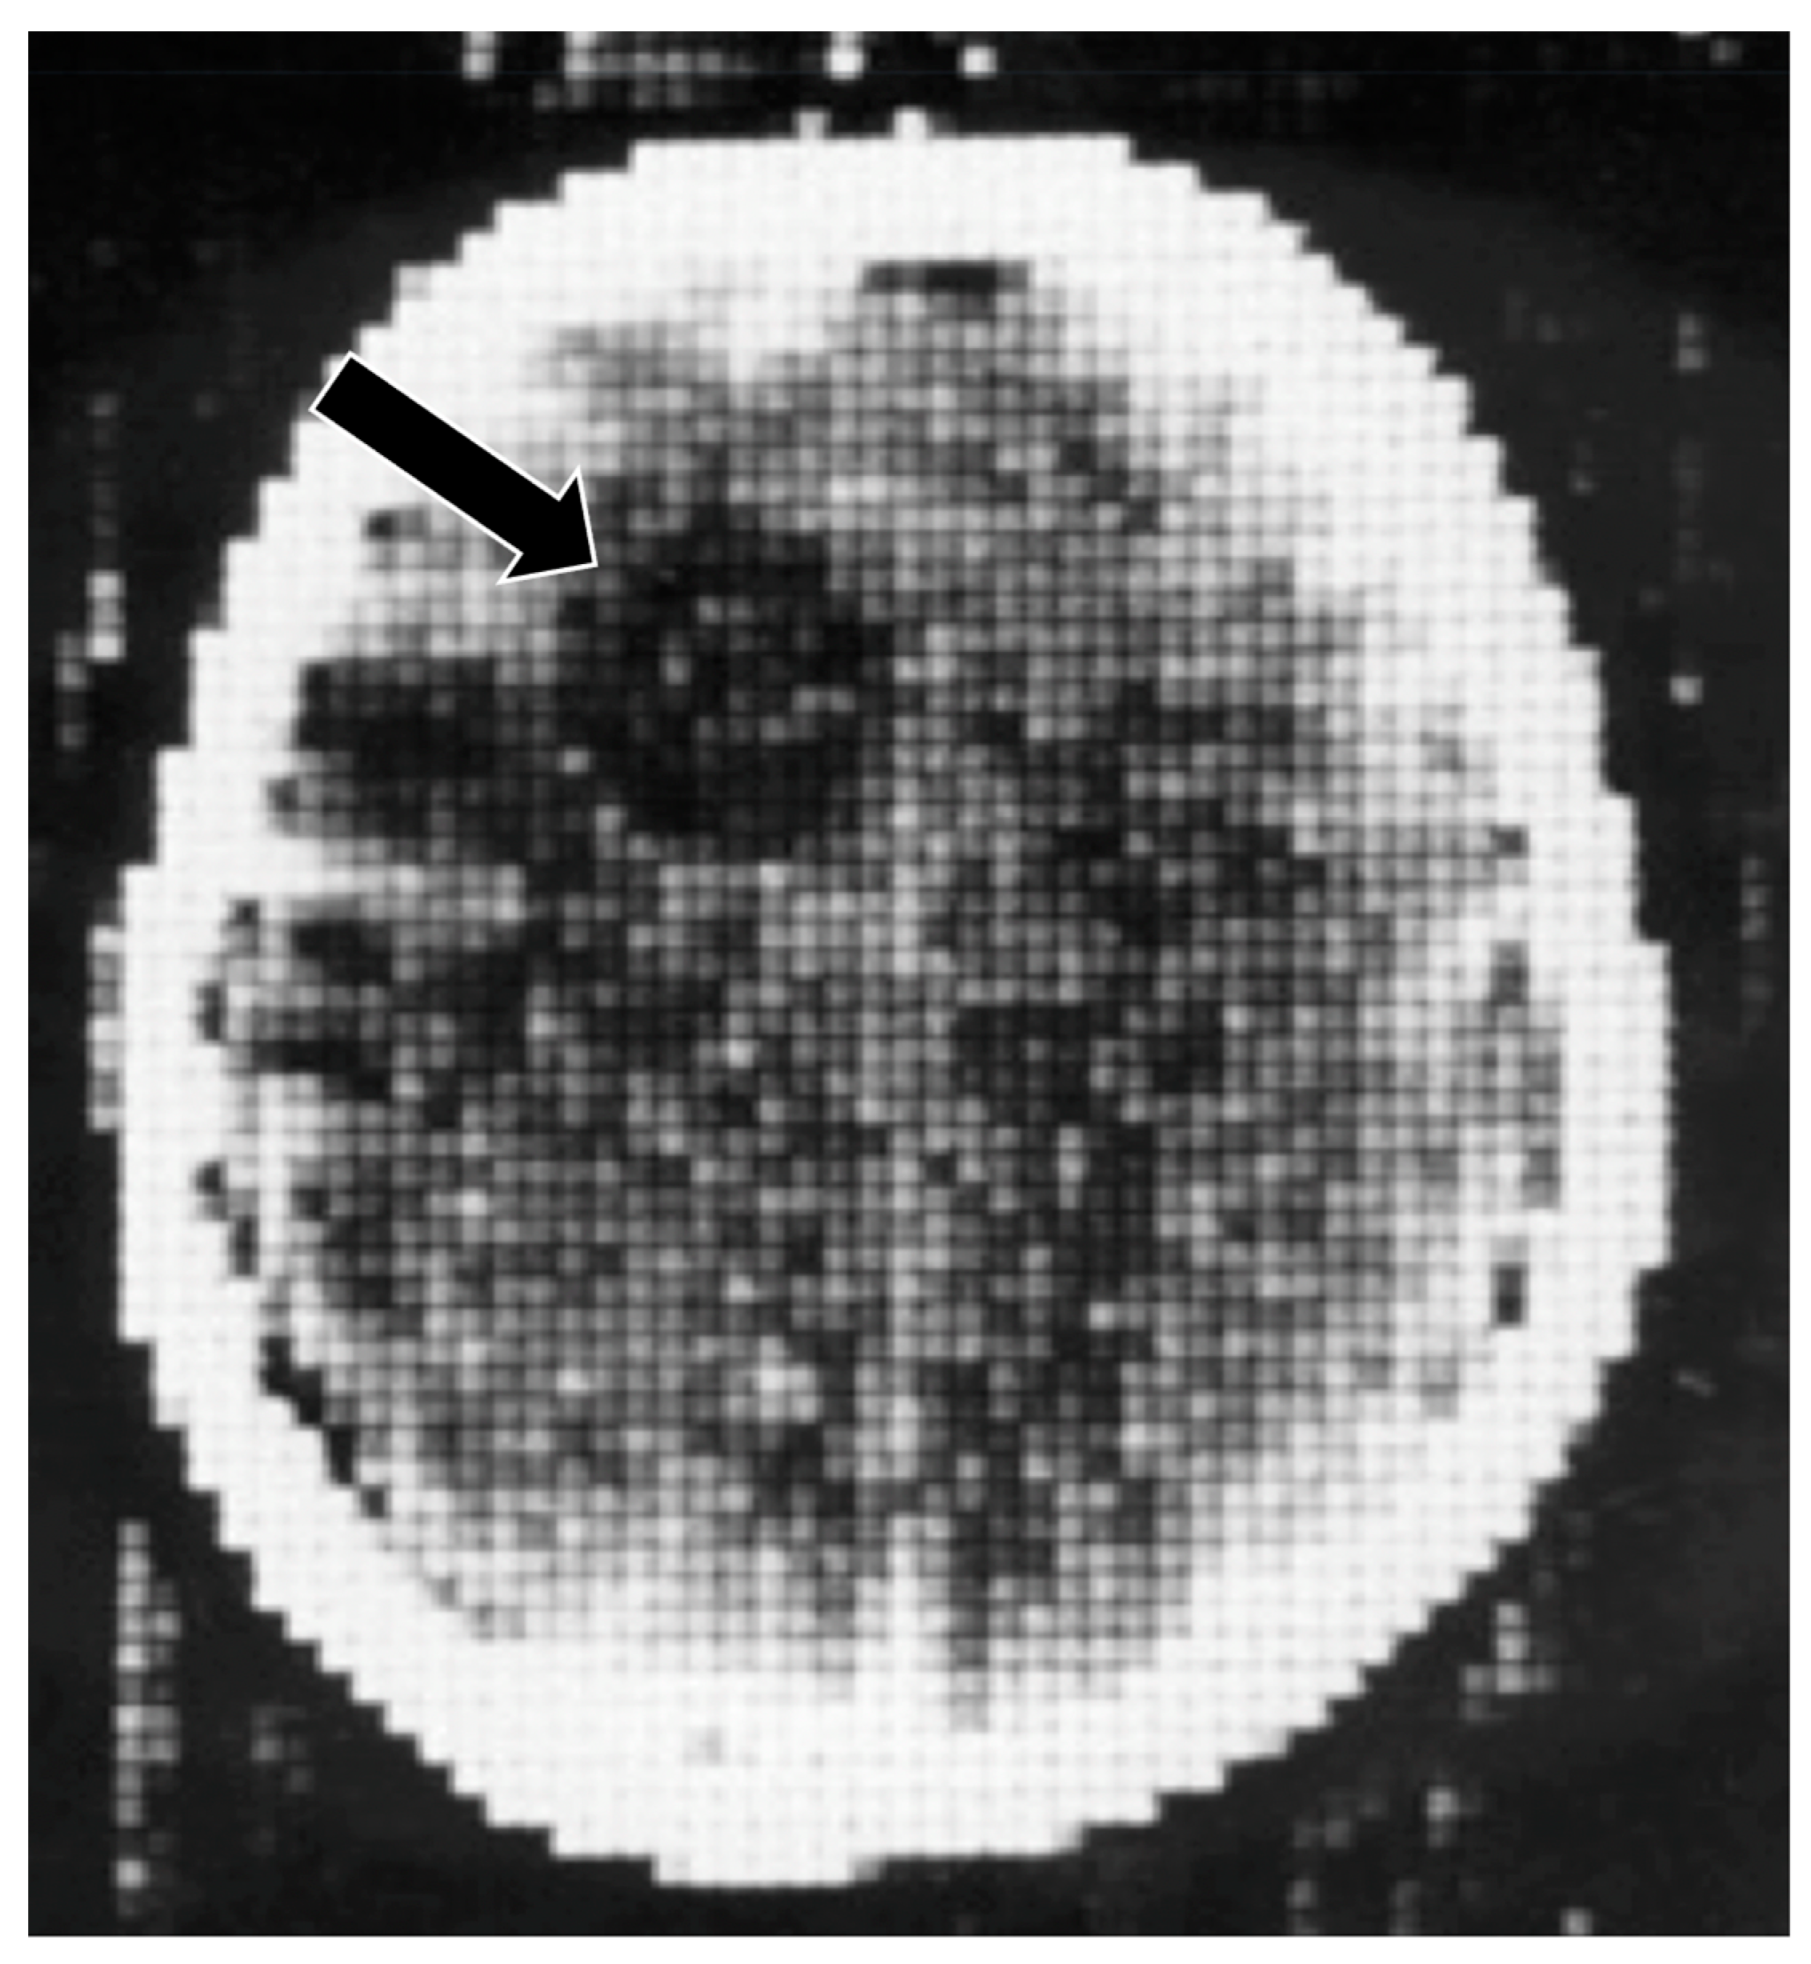

The first major revolution in soft tissue contrast in medical imaging came in 1971 with the introduction of brain computed tomography (CT) [5,6]. The technique not only produced slices of the brain that were much more useful than conventional tomography, but it directly displayed brain tissue. Within the brain, there was high intrinsic contrast between normal and abnormal tissues so that lesions such as the glioma shown in Figure 5 could readily be seen because its signal was lower than that of normal brain. The intrinsic contrast was present without requiring the use of a contrast agent (such as air and iodinated compounds). When intravenous iodinated contrast agents were used with CT, additional information was obtained. CT transformed the practice of neuroradiology from 1971 onwards, and body imaging from 1975 onwards as well (Figure 6).

Figure 5.

First patient examined with CT, frontal cystic glioma (October 1971) [5]. CT produced images of slices of the brain, which was a major improvement over conventional tomography. Signal is seen from the brain in this 80 × 80 matrix image. In addition, there is negative intrinsic contrast between the cystic glioma (black arrow) which is lower signal (darker) than the surrounding normal brain.